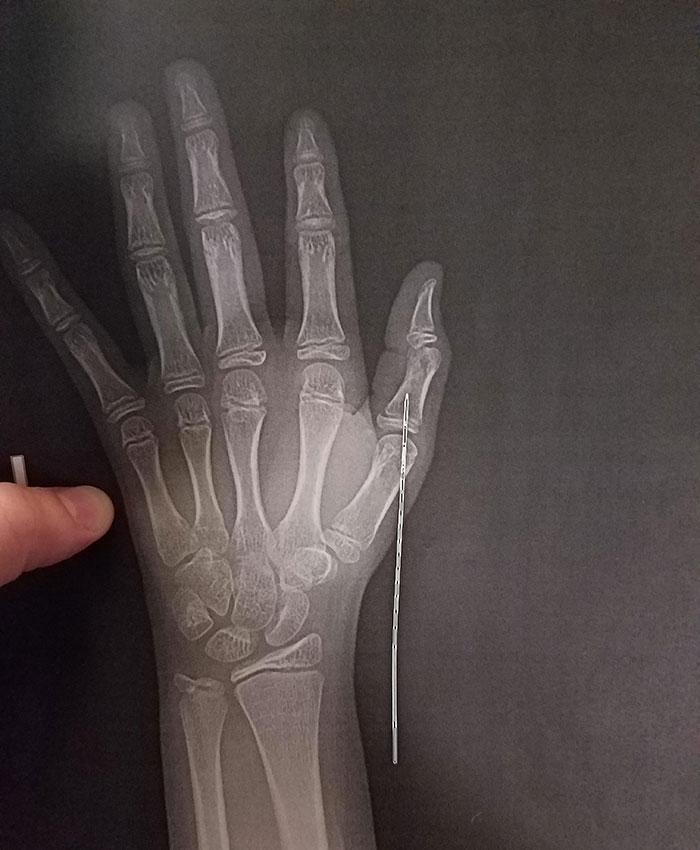

X-Ray Of Blow Dart In My Hand